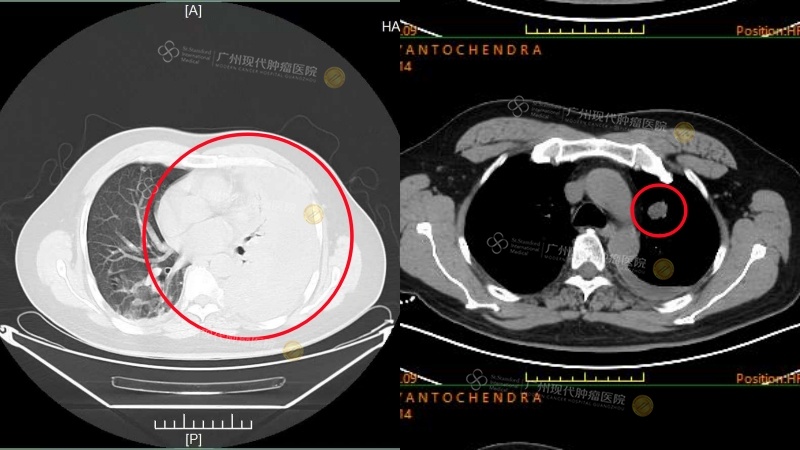

Seorang pasien kanker ginjal asal Indonesia, Tn. An (nama samaran), didiagnosis menderita karsinoma sel jernih ginjal di negaranya, namun tidak segera mendapatkan pengobatan yang efektif. Pada awal November 2024, saat datang ke rumah sakit, ia telah mengalami penyebaran kanker ke otak, paru-paru, dan beberapa bagian di tulang, serta kelumpuhan total. Setelah dilakukan diskusi dan evaluasi oleh tim MDT rumah sakit, dirumuskan rencana pengobatan individual berupa “terapi target dikombinasikan dengan imunoterapi”. Satu bulan kemudian, nyeri yang dialami Tn. An berkurang secara signifikan, dan kekuatan otot di kedua sisi tubuhnya mulai pulih secara bertahap. Evaluasi terakhir menunjukkan bahwa seluruh lesi metastasis dalam tubuhnya telah terkendali dengan baik. Kekuatan otot di kedua sisi pulih dari tingkat 1 menjadi tingkat 5, dan ia kini sudah dapat berdiri serta berjalan secara mandiri.

Paru-paru: Saat pertama kali dirawat di rumah sakit VS setelah pengobatan

Kedua tulang ilium: pada saat rawat inap kedua VS setelah pengobatan